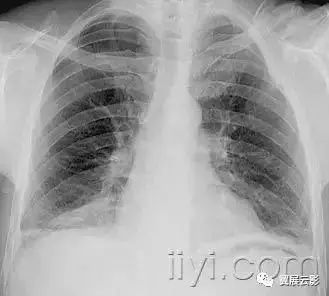

附图为小叶中心性肺气肿